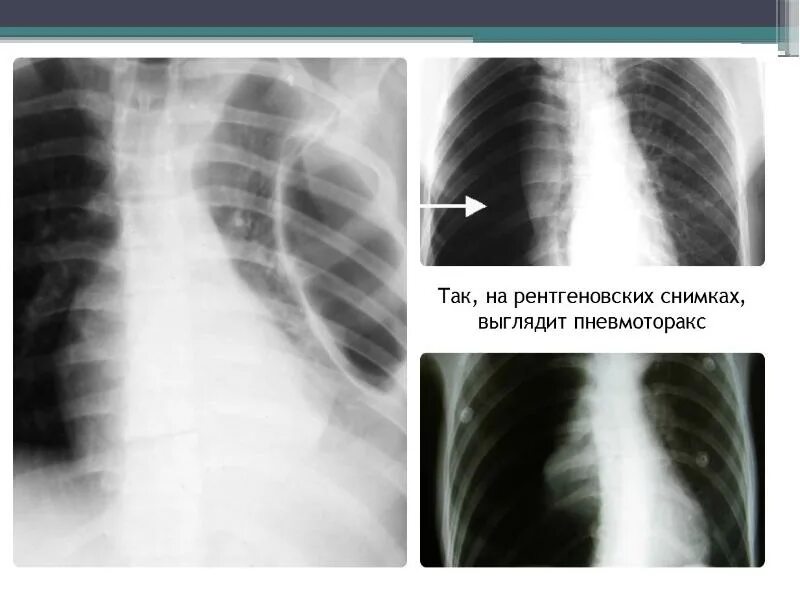

Закончился воздух в легких